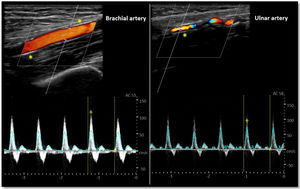

As for the venous circulation, arterial patency and diameter must be evaluated. Markers of arterial disease such as vascular calcification (hyperechogenic contour of the vessel sometimes severe enough that an acoustic shadow is seen),20 stenotic disease (post-stenotic doubling of peak systolic velocities indicates a >50% diameter reduction)20 and altered flow pattern must be assessed (Fig. 4). The upper arm arterial circulation is comprised of high resistance flow arteries and this will translate into triphasic flow pattern in the Doppler evaluation20 (Fig. 4). Alteration of the flow pattern (biphasic/monophasic flow) indicates diseased arteries (although this does not preclude access creation). Radial artery systolic peak velocity (SPV) measurement as well as artery flow rate are also useful, as a value below 50cm/s and below 50mL/min respectively, have been associated with higher rates of primary failure.30,31